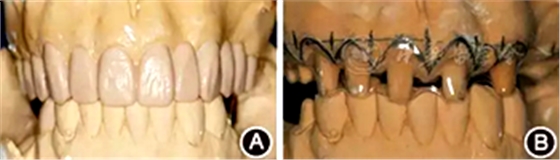

圖1 患者初診時臨床照片 A:正面微笑像;B:正面口內(nèi)像

(1)制作診斷蠟型:牙齦炎癥控制后,取研究模型,以上前牙中齦緣水平最高者為參考點,根據(jù)理想牙齦曲線形態(tài)、牙齦頂點位置及牙齦線協(xié)調(diào)對稱關(guān)系,擬定修復(fù)體邊緣和齦緣位置。結(jié)合上中切牙理想大小、形態(tài)、寬長比及恰當(dāng)?shù)慕佑|區(qū)長度制作診斷蠟型,模擬修復(fù)效果,根據(jù)診斷蠟型和術(shù)前照片,與患者溝通、結(jié)合其意見修改蠟型,確定最終修復(fù)體形態(tài)及齦緣位置(圖4A)。

圖4 術(shù)前制作診斷蠟型及手術(shù)導(dǎo)板 A:診斷蠟型,確定最終修復(fù)體的形態(tài)及齦緣位置;B:透明墊式手術(shù)導(dǎo)板,用以指導(dǎo)手術(shù)切口的精確控制